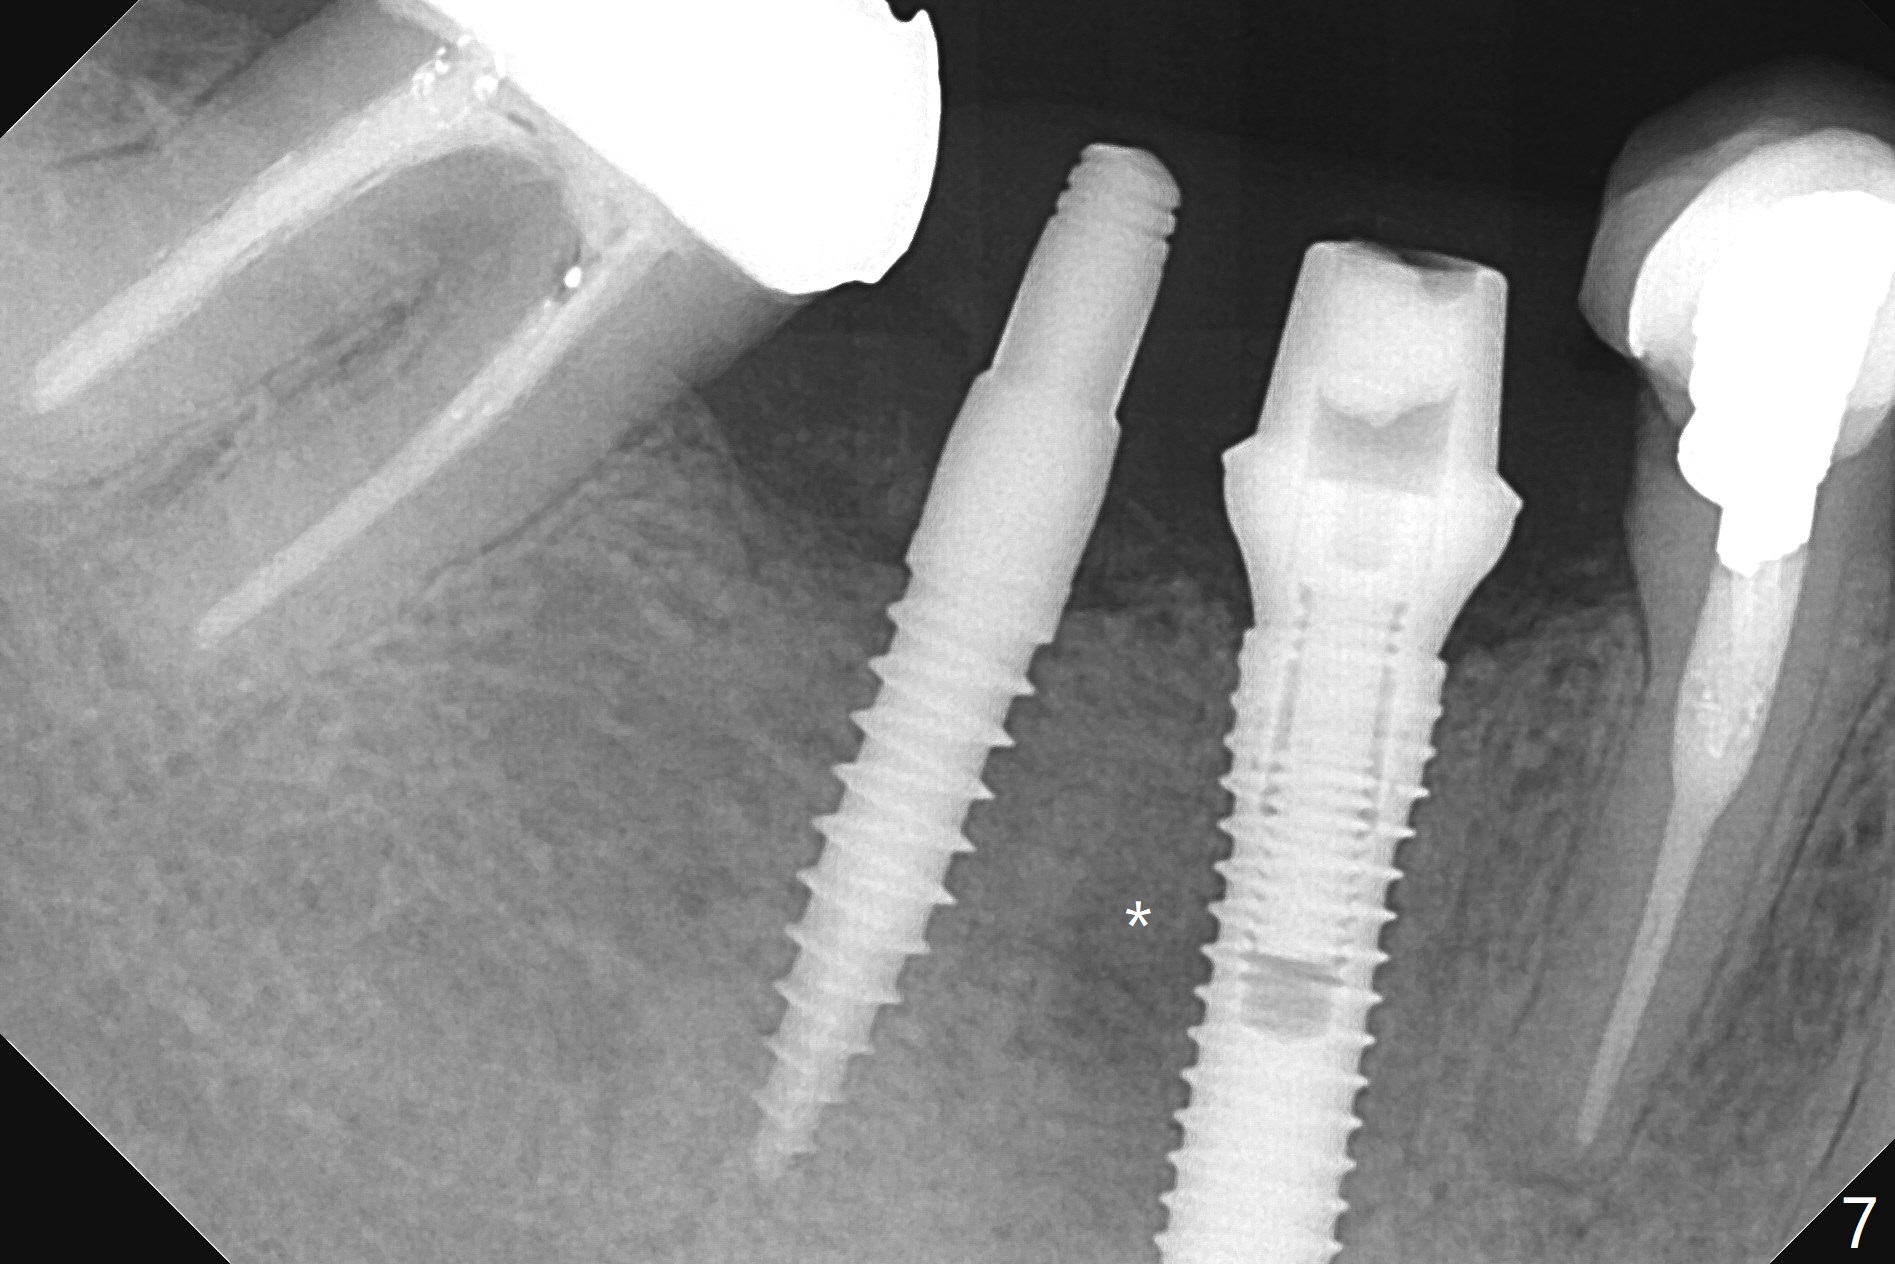

Preop examination shows that the buccal plate at #30 is atrophic (Fig.1 *). The mesiodistal width of the pontic is narrow as compared to the retainer at #31 (Fig.2). It appears that a narrow implant should be placed at #30 and should be able to sustain functional loading. After ridge reduction at #30 (Fig.3 ^) and extraction and debridement at #29, osteotomies at these sites are initiated with 1.2 mm and 2 mm drills, respectively. Probably due to low bone density, the osteotomy at #29 drops deep and close the Mental Loop (red dashed line). While the trajectory at #30 improves, the osteotomy at #29 remains close to the Mental Loop (Fig.4), asymptomatic with infiltration anesthesia. A 3x12(2) mm 1-piece implant is placed at #30 and 3.8x16 mm 2-piece implant at #29 (Fig.5,6 with insertion torque >50 and <50 Ncm, respectively). The large distal defect at #29 (Fig.3,5 *, most likely due to post-related perforation) is later filled with bone graft (data not shown). After placing an abutment at #29 and suturing, periodontal dressing is applied. Three months later, the meisal gap of #29 disappears while the distal one reduces (Fig.7 *). The abutment is changed to 4.5x4(4) mm one before reprep for impression. There is no bone loss 9 months post cementation (Fig.8) or 3 years 9 months post cementation (Fig.9). In fact the crown is lost at #31. At repeated request from the patient, a prefabricated post and crown will be fabricated for short term purpose while an implant is going to be placed at #19. The new crown at #31 has no occlusal contact (Fig.10), which may change over time.